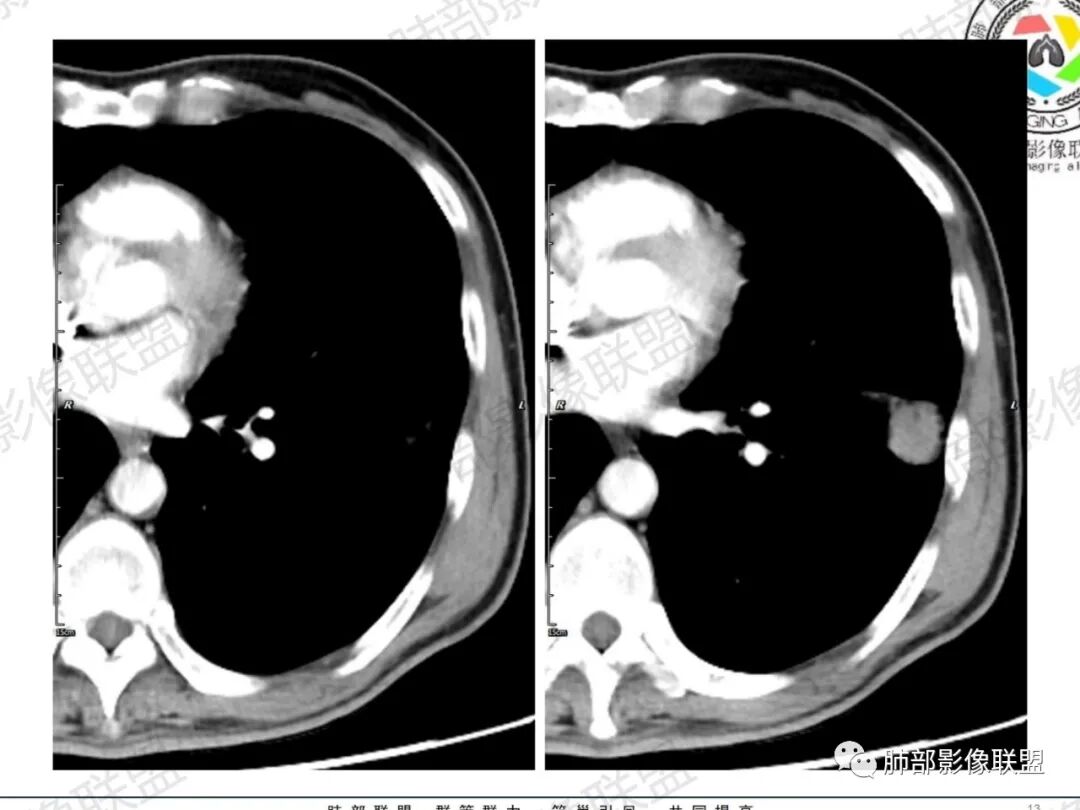

琦遇:恶性没有问题,肺气肿底子、病灶分叶、少许毛刺、叶间胸膜凹陷、部分边缘可见清晰的GGO、胸膜牵拉凹陷、局部胸水、近端支气管截断、部分支气管被推移、占位效应明显、强化特点为不均匀强化、内部有少许沼泽样低强化区,强化部分轻中强化为主、余肺可见转移性结节、左肺上叶似为囊腔型腺癌一枚,肿瘤标志物提示非小、神经内分泌,综合分析考虑大神泌、腺癌、腺鳞癌、鳞癌  同时左肺上叶囊腔型腺癌  肺转移

傅昌瑜:中老年男性,肺气肿背景,右胸背疼痛1周。CEA、NSE、CYFRA—211升高。左上肺混合磨玻璃结节,内见较多空泡和扩张支气管。左下肺胸膜下肿块,边缘较光滑,深分叶,似有血管进入,与支气管关系不清,内见不均匀强化,见沼泽地样坏死,有胸膜栽赃。另两肺多发圆形小结节。考虑恶性并肺内转移,多原发可能性大,左上肺腺癌,左下肺病理难以判断,小细胞癌?鳞癌?

蓝天白云:中年男性,肺气肿背景,左肺下叶肿块,边缘膨隆,有分叶,内有湖泊样坏死,有轻中度强化,局部胸膜栽赃,收缩力不强,周围见肺气肿征象。左肺上叶混合磨玻璃影,边界清楚,考虑都是恶性,左上肺iac,左下肺腺鳞癌,或大细胞肺癌可能。两肺多发结节,考虑转移

LCNEC最常见的影像特征包括:(1)肿块发生部位:周围型肺癌为主,少数发生于肺中央。(2)肿块大小及形态。因肿瘤细胞生长迅速常形成较大肿块,因此其体积一般较大,直径常在3~10cm范围内,病灶常为不规则形软组织肿块。(3)肿块边界。多数学者报道大多数肿块边界清晰,边缘呈分叶状,毛刺征及“胸膜凹陷征”少见,认为与该病对周围组织浸润较轻及较少产生纤维瘢痕组织牵拉有关联。(4)肿块密度、强化特点及代谢情况。据文献报道,该类肿瘤因体积较大CT上常见软组织肿块,且多数密度不均匀,内见囊变坏死区,增强后呈轻或中度不均匀强化(可见强化者占75.7%),认为其强化特点与其内部肉眼可见坏死灶和肿瘤较大直径有关。(5)伴随症状及远处转移。该病恶性程度高,侵袭性强,常侵犯邻近结构,如胸膜、心包、邻近骨质或纵隔内组织等,易出现纵隔淋巴结转移,部分发生肺内及远处转移,少数早期可出现广泛远处转移。